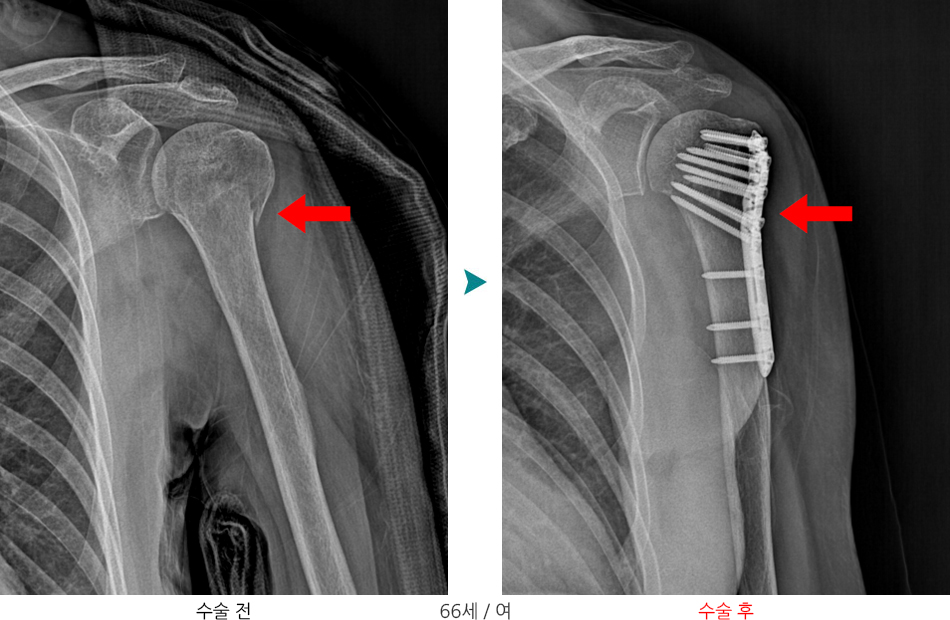

상완골 근위부 골절은 상완골(위팔뼈)의 머리 부분(견관절 가까이)에 생기는 골절입니다.

변위가 크거나 관절면을 침범한 골절의 경우

- 개방적 정복술 및 금속판/금속나사를 이용한 내고정술 시행